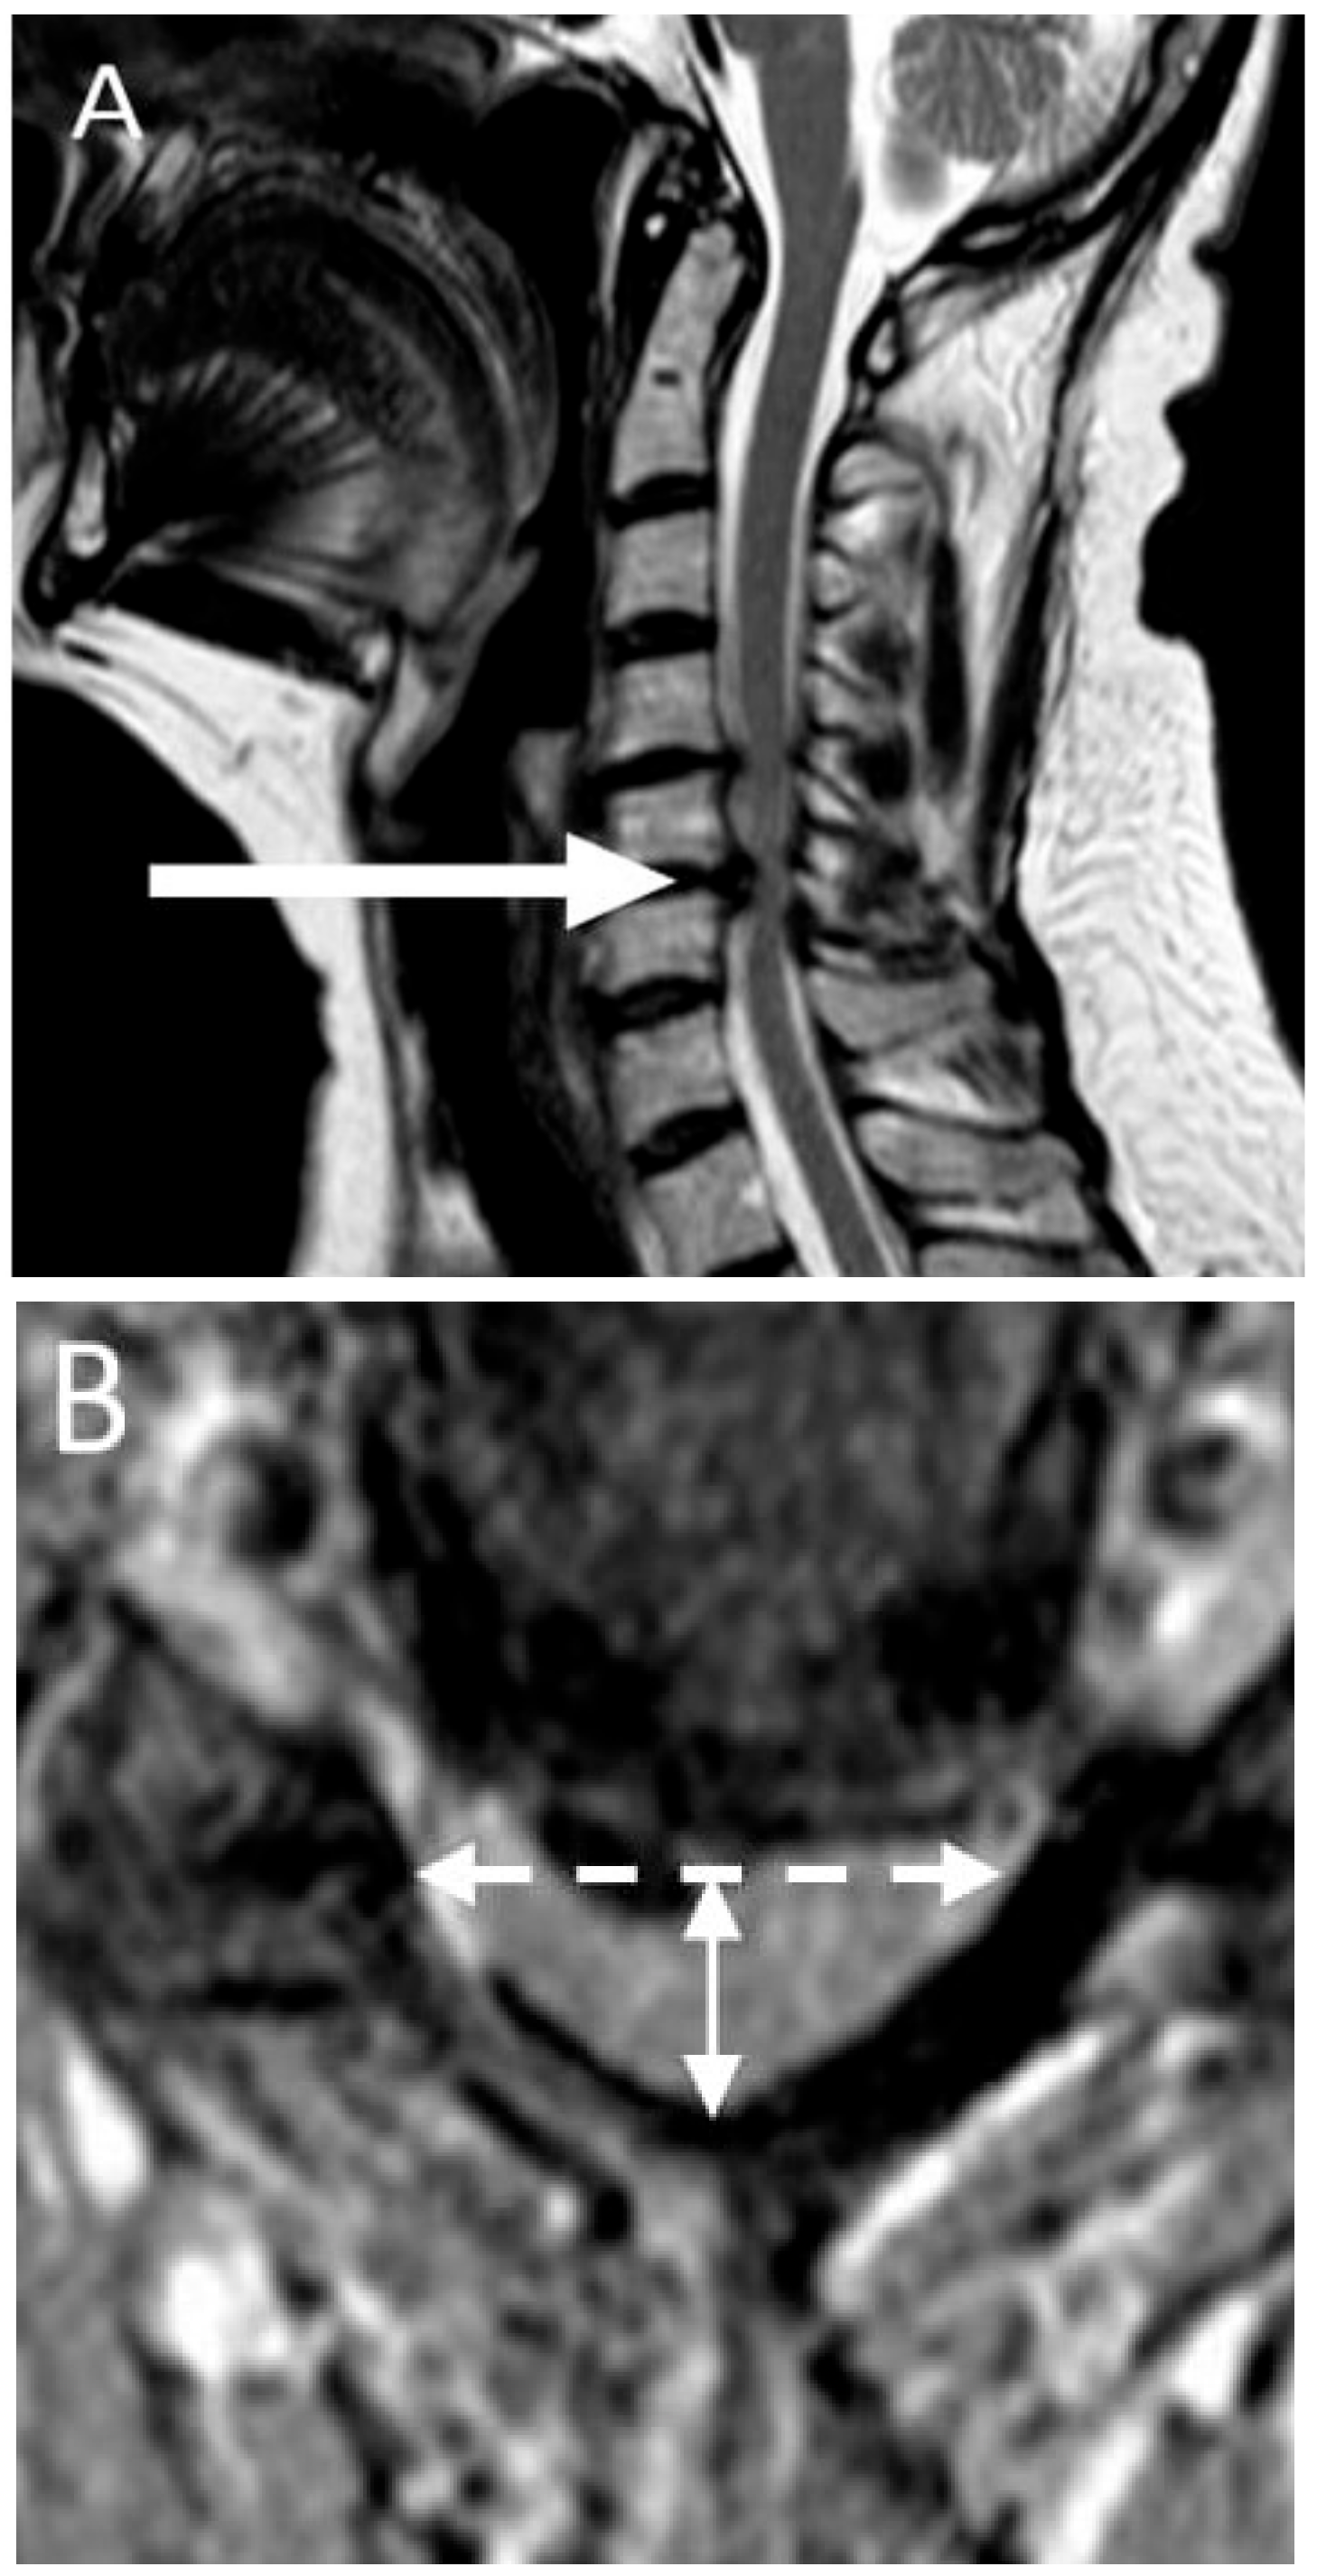

2.4. Imaging